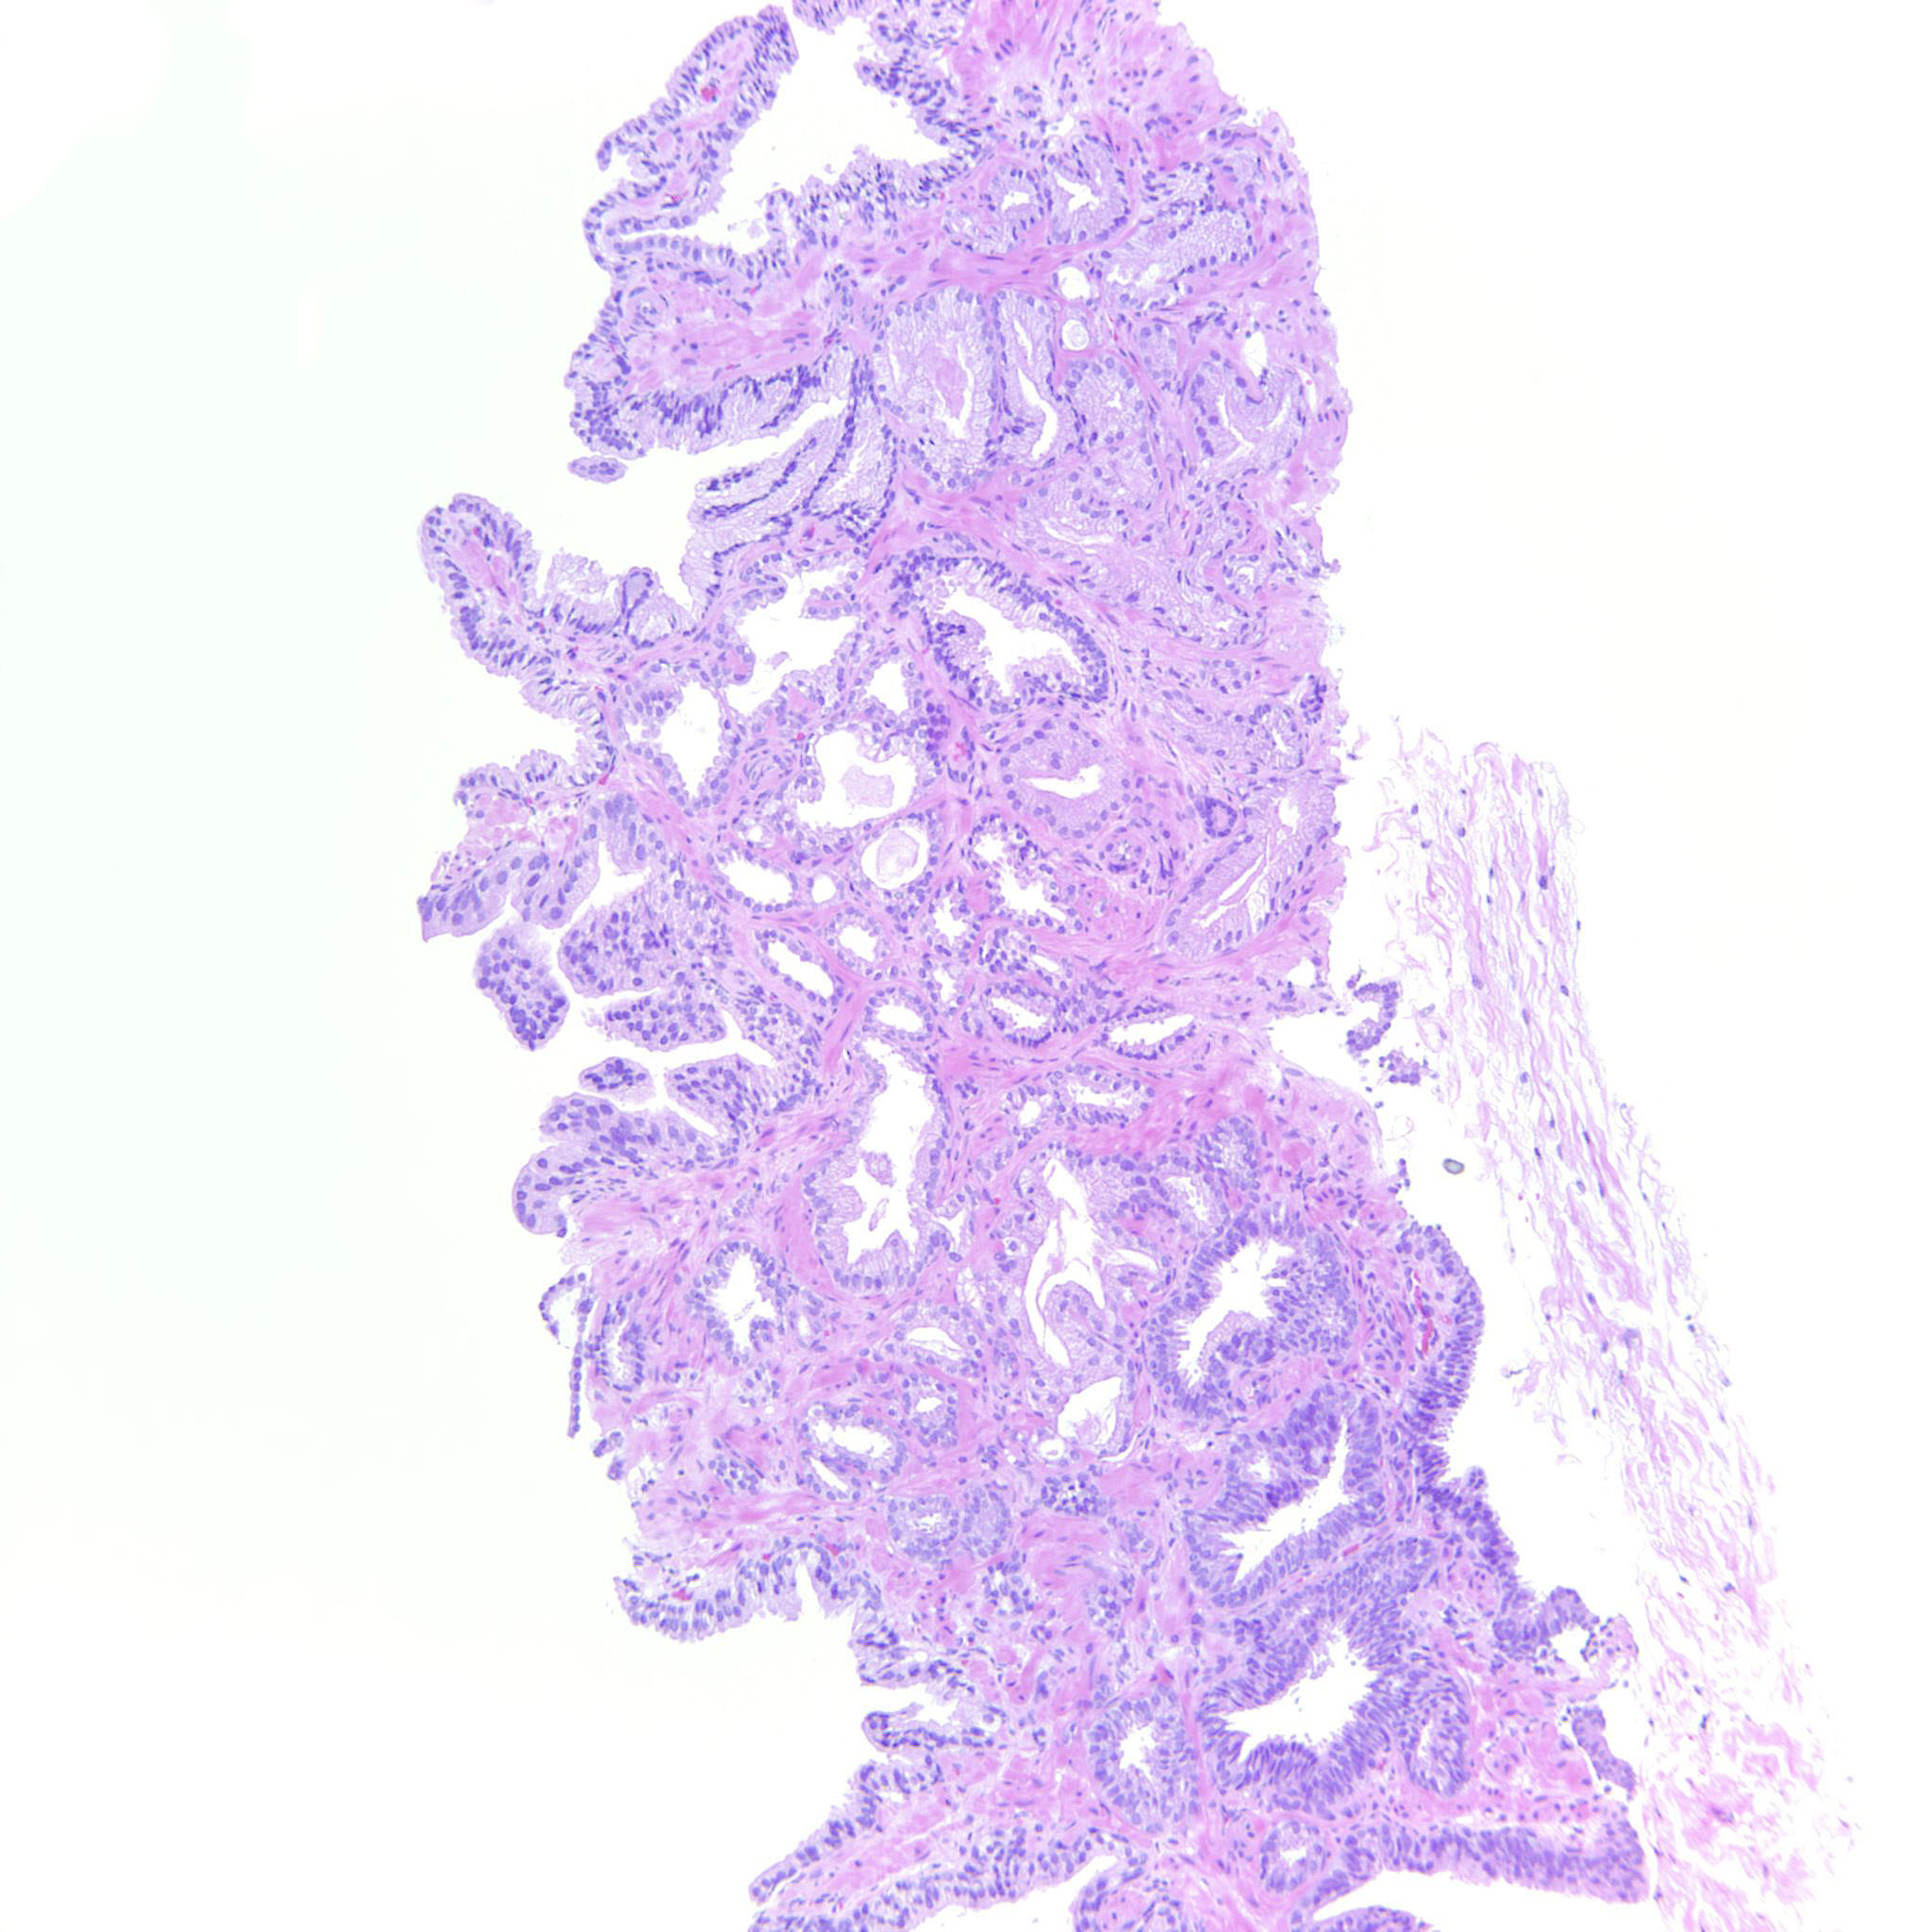

Prostate cancer grading

Case ID: 289